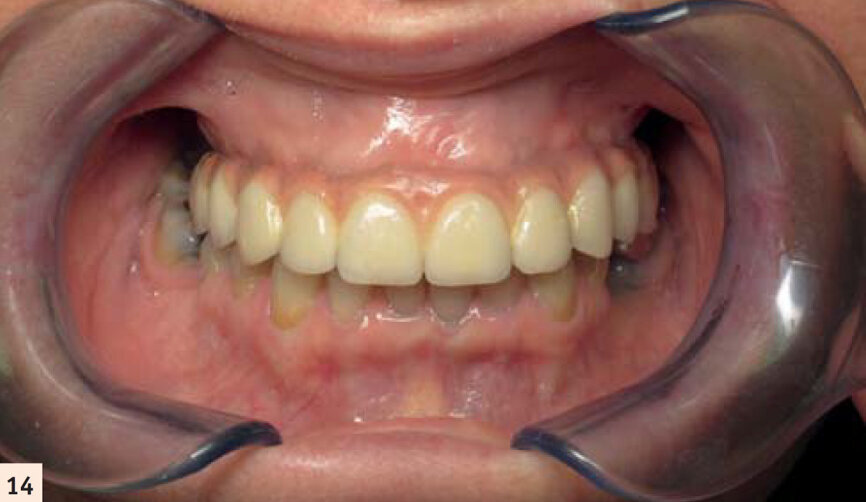

La céramique est maquillée pour s’approcher de l’aspect de dents naturelles. Une fausse gencive rose permet de palier au manque tissulaire préalable (Figs. 14, 15 et 16).Notre patiente a retrouvé ses dents et ne sera restée sans denture fixe que quelques heures. Les suites opératoires auront été minimes et la durée totale du traitement été de 4 mois.

Bridge céramométallique transvissé avec une fausse gencive.